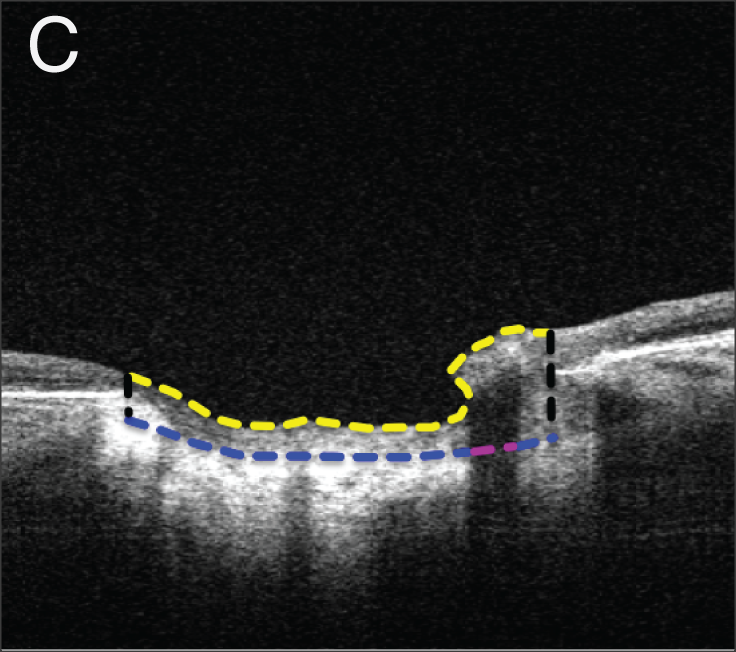

• Interplay between intraocular and intracranial pressure effects on the optic nerve head in vivo

• Z Zhu, S Waxman, B Wang, J Wallace, SE Schmitt, E Tyler-Kabara, H Ishikawa, JS Schuman, MA Smith, G Wollstein, IA Sigal

• Experimental eye research, 213, 108809, December 2021.